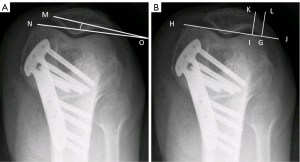

Bilateral standing anteroposterior whole-leg radiographs and anteroposterior, lateral, and axial radiographs were obtained from all patients before surgery and at the final follow-up. The whole-leg radiographs were acquired with a 14,351-inch cassette. The axial radiographs were obtained with knee flexion of 30° from the horizontal direction. As previously reported (3-5,12), measurements of the femoral tibial angle (FTA), medial proximal tibial angle (MPTA), and weight-bearing line percentage (WBLP) were obtained from whole-leg radiographs for the assessment of lower extremity alignment. FTA was measured as the angle formed by the intersection of the femoral and tibial mechanical axes. The femoral mechanical axis is the line from the center of the femoral head through the center of the knee, and the tibial mechanical axis is drawn as a line from the center of the ankle to the center of the knee (Figure 3). MPTA was the medial angle between two lines: one line of the tibial anatomical axis and a second line extending from the medial to the lateral most area of the tibial plateau, while excluding the osteophyte at the tibial plateau surface. Using a whole leg radiograph, the WBLP was calculated. The denominator was the width of the tibia as measured using a ruler, and the numerator was the tibial intersection of the weight-bearing line (with medial tibial edge at 0% and the lateral tibial edge at 100 %). Measurements of the Caton-Deschamps index (CDI) and Insall-Salvati index (ISI) were performed on a lateral view of the knee at a 30° flexion angle to assess the patellar height. Measurement of CDI and ISI were illustrated in Figure 4. Measurements of the lateral patellar tilt angle (LPTA) and lateral patellar shift (LPS) were illustrated in Figure 5. All images were imported into the same picture archiving and communications system. Measurements were made on radiographic images using standard digital tools, measuring to 0.1 accuracy (°). The image interpretation and measurements were performed by two senior readers (ML and ZL), who both had more than 10 years of experience in reading study radiographs. If readers disagreed on the measurements, readings were adjudicated by a panel of four readers (two non-author radiologists, ML and ZL).